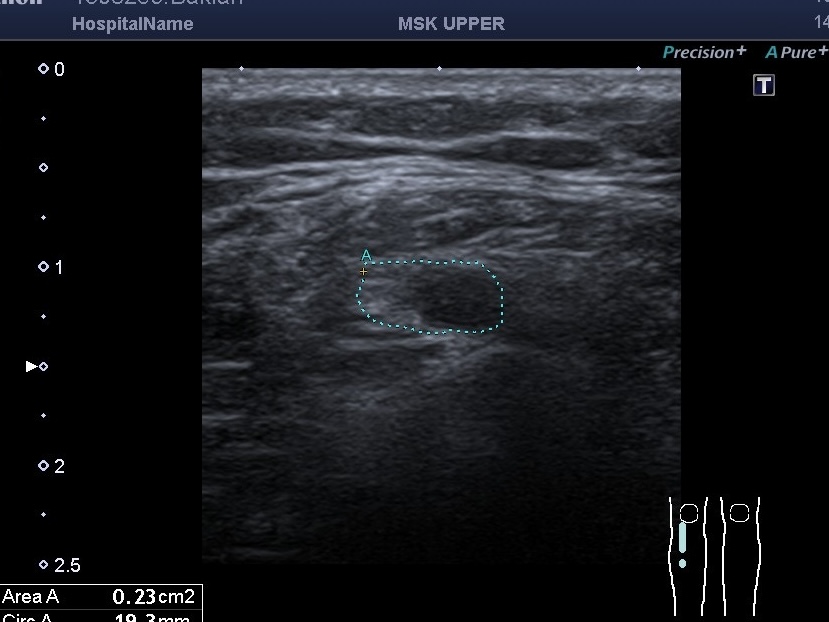

УЗД молочних залоз Medicinе groupПід час дослідження молочних залоз основну увагу лікар приділяє виявленню підозрілих утворень. УЗД молочних залоз особливо...

УЗД молочних залоз Київ. Крім різних видів пухлин молочної залози, нам часто зустрічаються також і запальні захворювання залози. Запальні неспецифічні...